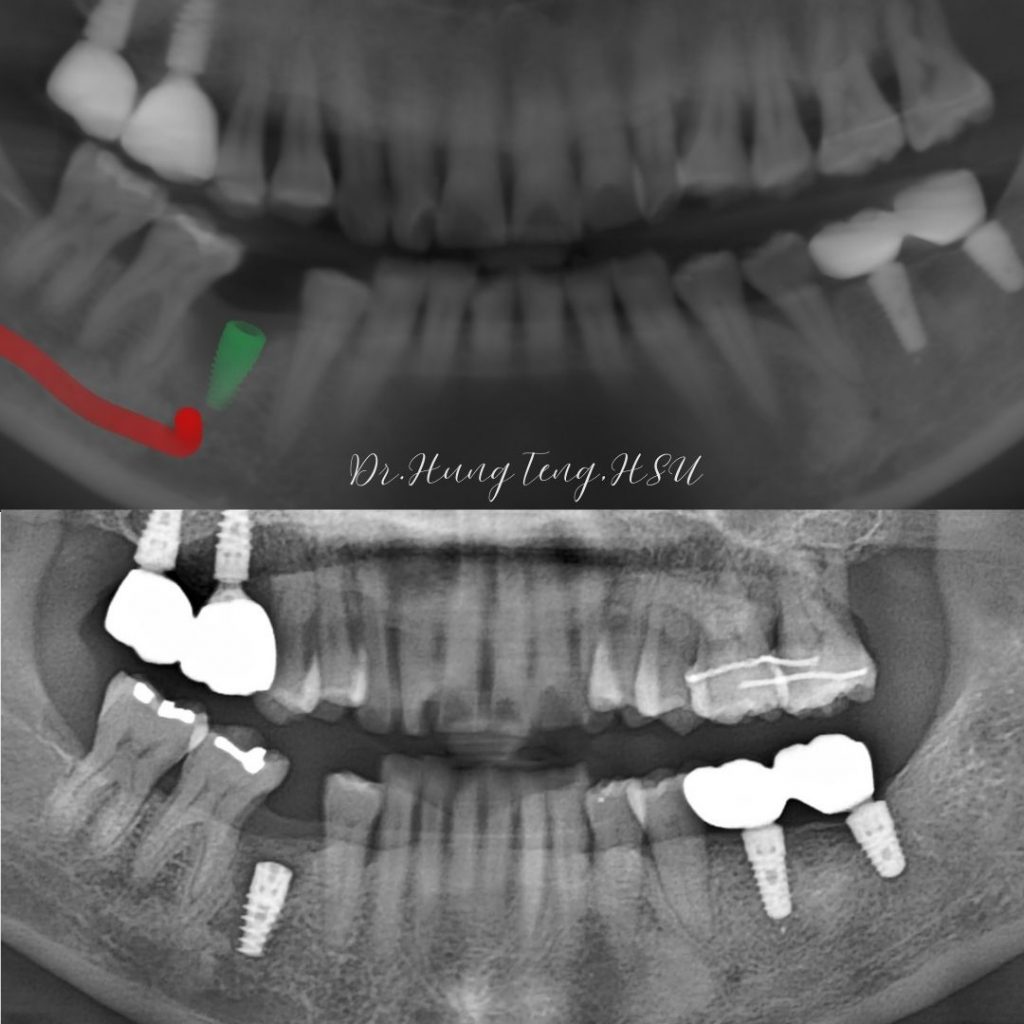

來試試百適達數位導板,讓植牙手術變得更方便、精準,帶給醫師和患者雙贏的完美體驗👏🏻

精準度是植牙手術成功的關鍵!有了百適達數位導板,醫師們能更快速規劃每一台手術,植體位置更精準,再也不怕「差一點點」的尷尬情況